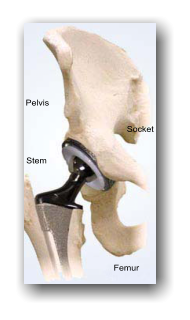

Within this website you will discover how an innovative procedure will find a way to make prosthesis surgery obsolete and has the potential to change outdated surgical procedures which are currently being used. With over 35 years of knowledge as an orthopaedic surgeon, Dr. Javier M. Cabrera, LMS. FICS. has envisioned an alternative surgical procedure to repair osteoarthritis and a myriad of problems damaged joints have disabled millions throughout the world. Dr. Cabreras’ vision has, and will continue to benefit health authorities, research centres, manufacturers of surgical instruments, surgeons and the ever growing number of patients world-wide who deserve a better alternative as opposed to current hip/ joint surgery. Dr. Javier M. Cabrera was the first surgeon who performed the first cemented total hip prosthesis implant surgery within a private clinic./ Lima, Perú, Current medical approaches towards osteoarthritis are mostly outdated due to the fact that the initial lesions in the articular cartilage, which triggers the destruction of the joint is treated with palliative therapies. This means the need for expensive and dreaded total joint prosthesis surgery is often required without need. Read on for details and facts on prosthesis surgery and the arthritic problems affecting millions of young and old patients suffering world-wide. In the not too distant past peptic ulcers were 'treated' by removing part of the stomach. Dentists were trained to aggressively remove patients teeth even if they had smaller cavities. Thankfully those barbarous methods are now obsolete as the world has evolved. However the treatment of osteoarthritis remains behind due to unnecessary total Joint replacement Surgery, which has created surgery complications and recovery. Added to this, palliative therapy, which initially reduces pain, unfortunately now accelerates the destruction of joints through wear and tare as a patients natural pain receptors are gradually dulled down. As the age of mortality expands, it is imperative that newer innovations become recognised and implemented. • Total hip prosthesis surgery remains highly invasive and aggressive: • Requires the removal of large amounts of healthy bone • Most healthy bone is replaced with metal prosthesis • Hip replacement surgery destroys the integrity of joint capsules • Expensive to the health provider and patient, with long and immobile recovery periods to patients of any age. • An increased risk of post-operative complications such as component failure, infection and metal corrosion. • Total Hip Prosthesis Surgery has historically held a high economic and environmental prize tag. • A new and innovative approach to perform arthroscope to reshape and resurface joints with bio materials will repair lesions as soon as they are diagnosed which will prevent osteoarthritis and its debilitating consequences. • Prosthesis surgery is synonymous to the old methods of dentistry when it was standard practise to remove teeth rather than drill out decay, then resurface the tooth. • The current procedure for Osteoarthrosis surgery is to remove most of the bone structure to treat a superficial problem. • Utilizing the Bio Hip method, its possible to reshape and resurface joint surfaces with Bio materials.

Within this website you will discover how an innovative procedure will find a way to make prosthesis surgery obsolete and has the potential to change outdated surgical procedures which are currently being used. With over 35 years of knowledge as an orthopaedic surgeon, Dr. Javier M. Cabrera, LMS. FICS. has envisioned an alternative surgical procedure to repair osteoarthritis and a myriad of problems damaged joints have disabled millions throughout the world. Dr. Cabreras’ vision has, and will continue to benefit health authorities, research centres, manufacturers of surgical instruments, surgeons and the ever growing number of patients world-wide who deserve a better alternative as opposed to current hip/ joint surgery. Dr. Javier M. Cabrera was the first surgeon who performed the first cemented total hip prosthesis implant surgery within a private clinic./ Lima, Perú, Current medical approaches towards osteoarthritis are mostly outdated due to the fact that the initial lesions in the articular cartilage, which triggers the destruction of the joint is treated with palliative therapies. This means the need for expensive and dreaded total joint prosthesis surgery is often required without need. Read on for details and facts on prosthesis surgery and the arthritic problems affecting millions of young and old patients suffering world-wide. In the not too distant past peptic ulcers were 'treated' by removing part of the stomach. Dentists were trained to aggressively remove patients teeth even if they had smaller cavities. Thankfully those barbarous methods are now obsolete as the world has evolved. However the treatment of osteoarthritis remains behind due to unnecessary total Joint replacement Surgery, which has created surgery complications and recovery. Added to this, palliative therapy, which initially reduces pain, unfortunately now accelerates the destruction of joints through wear and tare as a patients natural pain receptors are gradually dulled down. As the age of mortality expands, it is imperative that newer innovations become recognised and implemented. • Total hip prosthesis surgery remains highly invasive and aggressive: • Requires the removal of large amounts of healthy bone • Most healthy bone is replaced with metal prosthesis • Hip replacement surgery destroys the integrity of joint capsules • Expensive to the health provider and patient, with long and